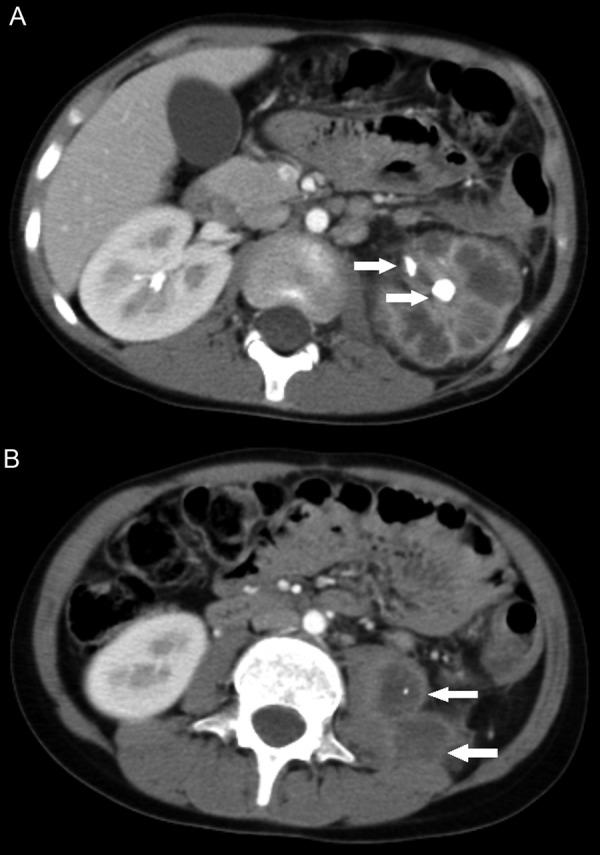

Antiglomerular basement membrane (anti-GBM) antibody disease is uncommon in the pediatric population. There are no cases in the literature describing the development of anti-GBM disease following XGP or nephrectomy. We report the case of a 7-year-old boy with no past history of urological illness, treated with antimicrobials and nephrectomy for diffuse, unilateral xanthogranulomatous pyelonephritis (XGP). Renal function and ultrasound scan of the contralateral kidney postoperatively were normal. Three months later, the child represented in acute renal failure with rapidly progressive glomerulonephritis requiring hemodialysis. Renal biopsy showed severe crescentic glomerulonephritis with 95% of glomeruli demonstrating circumferential cellular crescents. Strong linear IgG staining of the glomerular basement membranes was present, in keeping with anti-GBM disease. Circulating anti-GBM antibodies were positive. Treatment with plasma exchange, methylprednisolone, and cyclophosphamide led to normalization of anti-GBM antibody titers. Frequency of hemodialysis was reduced as renal function improved, and he is currently independent of dialysis with estimated glomerular filtration rate 20.7 mls/min/1.73 m. Case studies in the adult literature have reported the development of a rapidly progressive anti-GBM antibody-induced glomerulonephritis following renal surgery where patients expressed HLA DR2/HLA DR15 major histocompatibility (MHC) antigens. Of note, our patient also expresses the HLA DR15 MHC antigen.

抗肾小球基底膜(anti-GBM)抗体病在儿科人群中并不常见。文献中没有描述XGP或肾切除术后发生抗GBM病的病例。我们报告了一名7岁男孩的病例,该男孩既往无泌尿系统疾病史,因弥漫性单侧黄色肉芽肿性肾盂肾炎(XGP)接受抗菌药物治疗及肾切除术。术后对侧肾功能及超声检查均正常。三个月后,该患儿出现急性肾衰竭,伴有快速进展性肾小球肾炎,需要进行血液透析。肾活检显示严重的新月体性肾小球肾炎,95%的肾小球呈现环形细胞性新月体。肾小球基底膜有强烈的线性IgG染色,符合抗GBM病。循环抗GBM抗体呈阳性。血浆置换、甲泼尼龙和环磷酰胺治疗使抗GBM抗体滴度恢复正常。随着肾功能改善,血液透析频率降低,他目前已无需透析,估计肾小球滤过率为20.7 ml/min/1.73 m²。成人文献中的病例研究报告了肾手术后发生快速进展性抗GBM抗体诱导的肾小球肾炎,这些患者表达HLA DR2/HLA DR15主要组织相容性(MHC)抗原。值得注意的是,我们的患者也表达HLA DR15 MHC抗原。